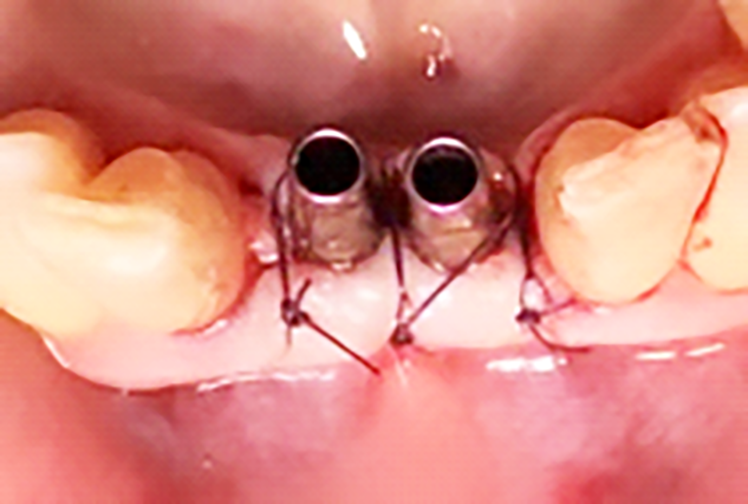

Si effettua la chirurgia implanto protesica guidata con mascherina (figura 8), si posizionano gli impianti 3.25 x 13 mm con un torque di 25 N (figura 9), si inseriscono i pilastri definitivi e si sutura (figura 10). Lo stesso giorno vengono ribasati e consegnati i provvisori solidarizzandoli con composito agli elementi 32-42 (figura 11).

Si effettua una radiografia di controllo dopo il posizionamento degli impianti e dei provvisori (figura 12).

In seguito all’estrazione degli elementi 3.1 e 4.1 si osserva a una settimana di follow up la perfetta guarigione dei siti (figure 4-5). I successivi follow up mostrano come la rigenerativa abbia ristabilito gli adeguati volumi ossei e grazie all’analisi tridimensionale dei siti implantari è possibile pianificare correttamente il posizionamento degli impianti (figura 6).